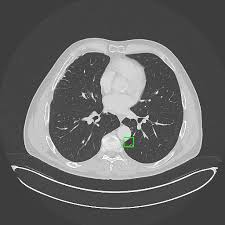

폐암은 폐에 있는 세포가 비정상적으로 증식하는 질환으로, 크게 비소세포폐암과 소세포폐암으로 나뉩니다. 대부분은 비소세포폐암에 해당하며, 소세포폐암은 진행이 빠르고 전이가 잘 되는 특징이 있습니다.

폐는 산소와 이산화탄소를 교환하는 중요한 기관이므로, 암이 발생하면 호흡 기능에 치명적인 영향을 줍니다.

특히 흡연력 있는 40세 이상 성인은 저선량 CT 검진을 권장합니다.